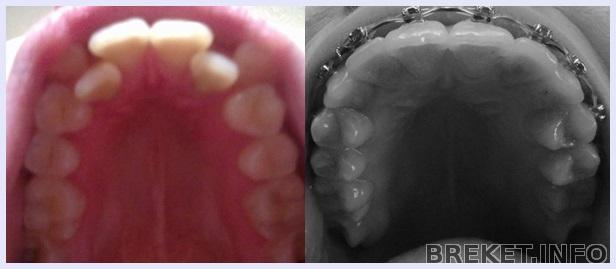

Нечего было делать и я решила сравнить изменения своего прикуса

2 месяца-5 месяцев- 9 месяцев

мою радость словами просто не описать